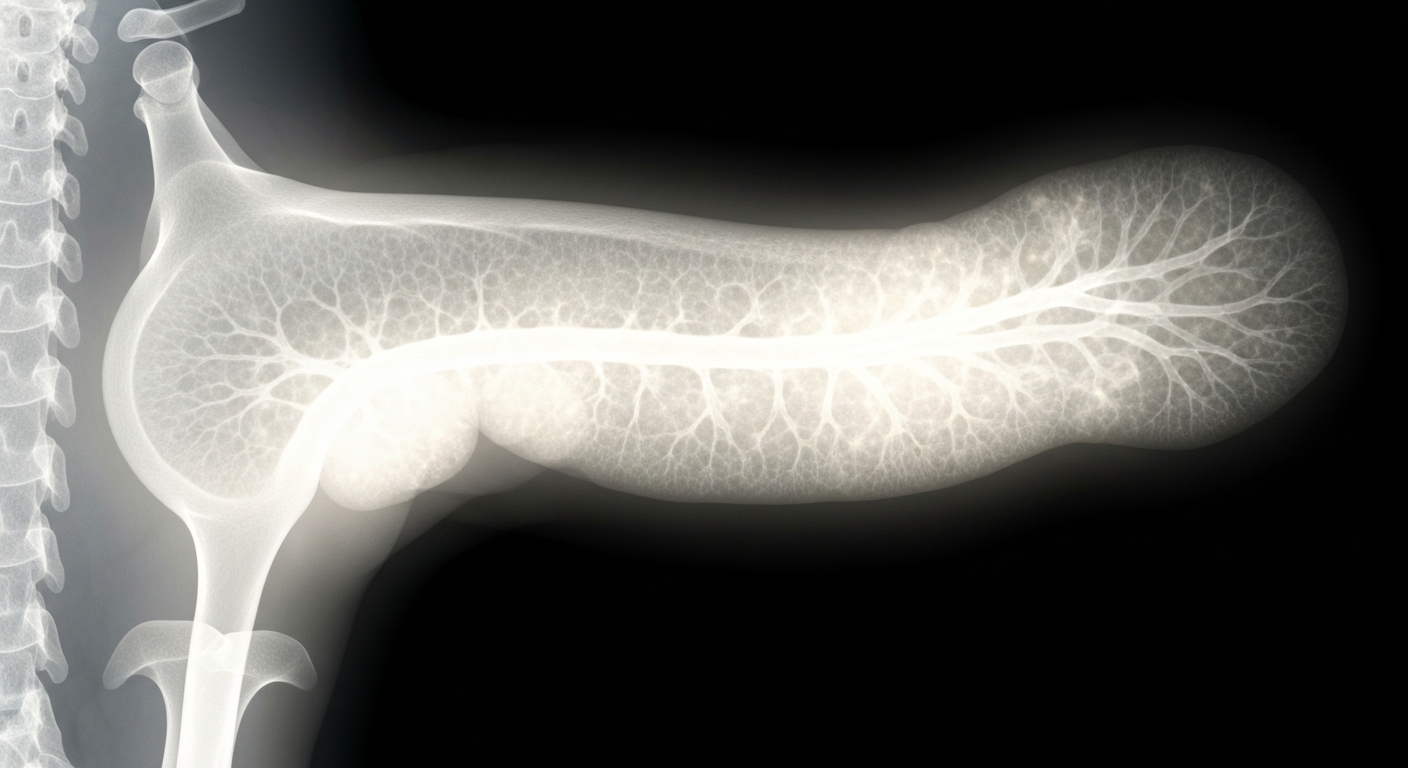

Cutting-edge imaging technology offers a glimpse into the complex inner workings of an aggressive pancreatic tumor, highlighting the potential of novel therapies to target these hard-to-treat cancers.Irvine TodayImPact Biotech, a clinical-stage biotech company, announced positive preliminary results from its ongoing Phase 1 study of Padeliporfin Vascular Targeted Photodynamic (VTP) therapy in patients with unresectable locally advanced pancreatic ductal adenocarcinoma (LA-PDAC). The data, to be presented at the Society of Interventional Radiology (SIR) 2026 Annual Meeting, showed that 66% of patients in the lowest dose cohort were able to undergo surgery following VTP treatment, with a consistent and well-tolerated safety profile. The company plans to continue advancing the LA-PDAC program while pursuing strategic partnerships to support commercialization of its late-stage upper tract urothelial carcinoma (UTUC) program.